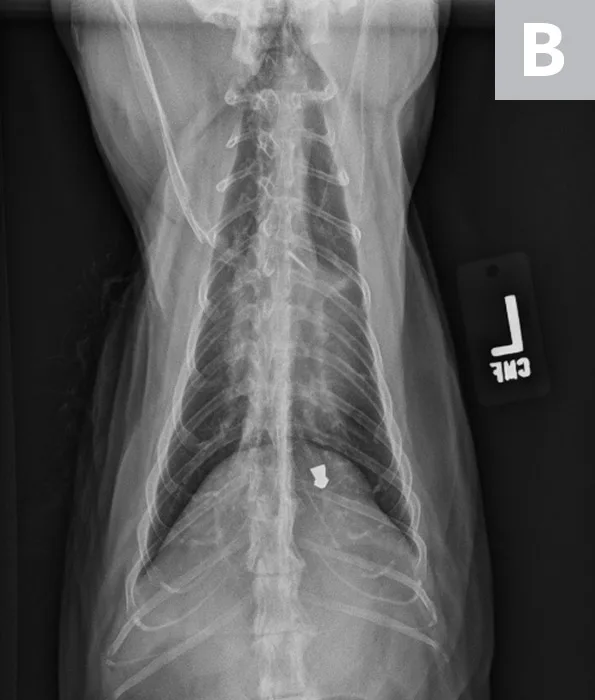

A 12-year-old neutered male domestic shorthair cat was presented for evaluation of a previously diagnosed heart murmur. On physical examination, a grade III-IV/VI left parasternal systolic murmur was auscultated. All other physical examination findings were within normal limits. There is history of right thoracic limb lameness and mild lytic lesions on the right humerus. Thoracic radiographs revealed mild to moderate cardiac silhouette enlargement with VHS 8.5, suggestive of cardiac disease (Figure 2). Additional cardiac diagnostic investigation (eg, total thyroxine, echocardiography) is recommended, and medical treatment should be considered.

VHS calculation in a cat diagnosed with HCM using a right lateral radiograph (A). L (ie, long axis; 5.0) is drawn from the carina to the most ventral aspect of the apex. S (ie, short axis; 3.5) is drawn perpendicular to L at the widest aspect of the heart, extending to the cranial and caudal borders. S and L are transposed along the spine from the cranial aspect of T4 using calipers. The number of vertebrae traversed (rounded to the nearest tenth) are summed to calculate VHS (8.5). Pulmonary vasculature is prominent but within normal limits, and there is a ballistic metallic foreign body (likely a bullet) in the dorsal subcutaneous tissue of the caudal thorax. Moderate spondylosis deformans exists at T13-L1 and L1-L2, and there is bridging spondylosis deformans at T10-T11. Intervertebral disk space at T10-T11 is collapsed, and there is fusion at the 2 vertebral bodies. Orthogonal radiograph of the patient is also shown for more complete evaluation of cardiac silhouette (B).